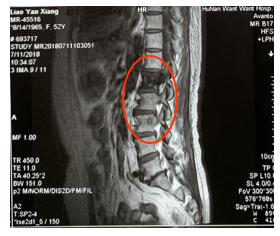

2018年7月11日出现腰痛,核磁共振MRI(如图3)示:腰椎1和腰椎3有转移,肺,胸椎转移同前。PFS1为16个月。

图3 MRI示腰椎1,3有转移